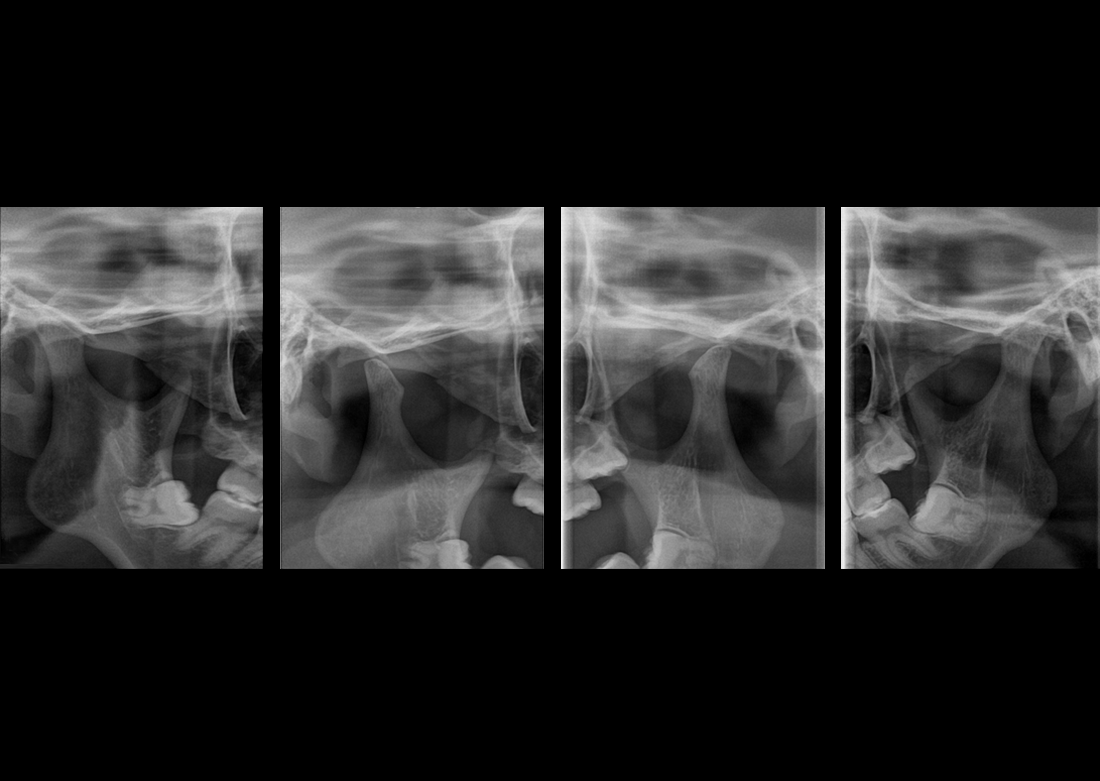

ULTRAGYORS KEFALOMETRIA*

A gyors szkennelési idő csökkenti a páciens mozgásából eredő képtorzulást, és alacsony dózis mellett minimalizálja a sugárterhelést.

KLİNIKAI KÉPEK

Kiváló diagnosztikai képalkotás több éves tapasztalattal és szakértelemmel.